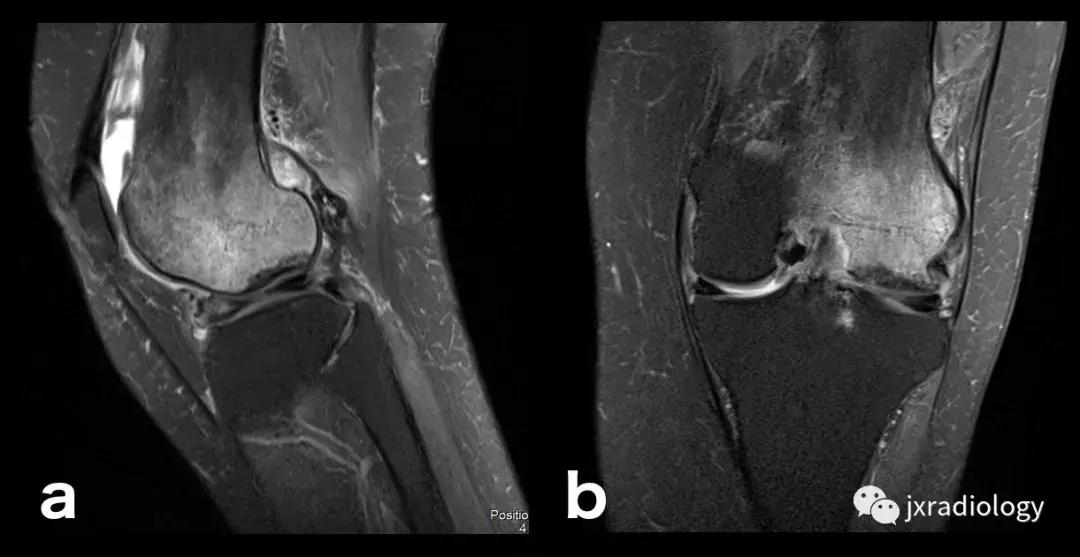

图18:剥脱性骨软骨炎(OCD)。OCD的病因学是未知的,可能是多因素的,包括损伤,血管因素,压力变化,发育差异和遗传学等。膝关节OCD最常见的部位是股骨内侧髁(75%)。这里显示了特征性的MRI表现,通常没有其它的损伤:在骨软骨碎片周围(b)有明显的小片骨髓水肿。(a,b:冠状T1-WI和冠状PD-FS-WI)。

图19:剥脱性骨软骨炎(OCD)。与图18相同的患者。X线片显示右侧股骨内侧髁见骨软骨碎片。

图20:患有血红蛋白病的患者(例如镰状细胞性贫血),在这种情况下,容易发生继发于毛细血管阻塞的骨坏死。这种阻塞导致毛细血管静水压升高,造成水敏性序列中低信号骨梗死周围的高信号水肿。这是充血性骨髓水肿的一个例子(由于骨髓空间毛细血管床液体流出受损)。该患者还表现出广泛的红骨髓转化,如T1-WI中的骨髓信号所示(远低于周围脂肪组织并略高于肌肉组织)和DP-FS-WI(未完全饱和,保持略高信号)( a:冠状面DP-FS-WI; b:冠状面T1-WI; c:轴向T1-WI; d:矢状面DP-FS-WI)。

图21:这名患者的炎症性关节炎表现为围绕内侧股 - 胫室侵蚀性改变的骨髓水肿。它是血管源性骨髓水肿的一个例子(继发于血液和血清传递至骨髓空间毛细血管床)(a,b:冠状T1-WI和PD-FS-WI)。